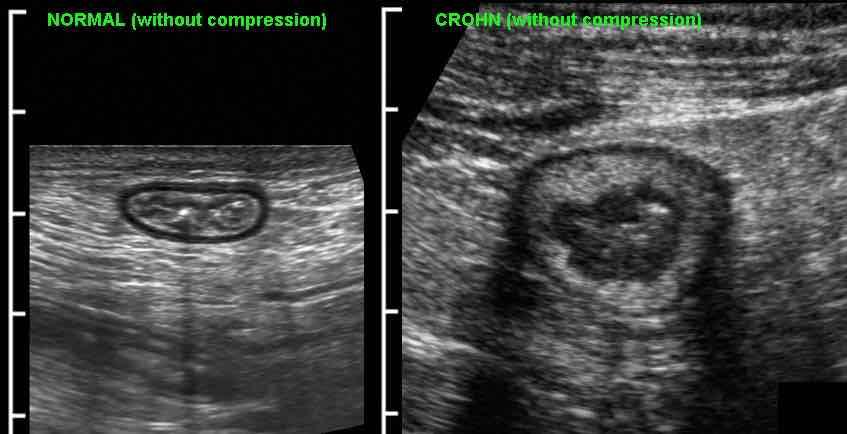

Đo độ dày thành ruột được thực hiện tốt nhất và có tính tái lập cao nhất trong khi ép, như ở đây trên một người bình thường (bên trái) và ở một bệnh nhân mắc bệnh Crohn (bên phải).

Các phép đo được thực hiện từ bờ ngoài của lớp cơ đến phía đối diện, sau đó chia cho 2, cho kết quả độ dày thành lần lượt là 1,5 mm và 6,5 mm đối với hồi tràng bình thường và hồi tràng Crohn.